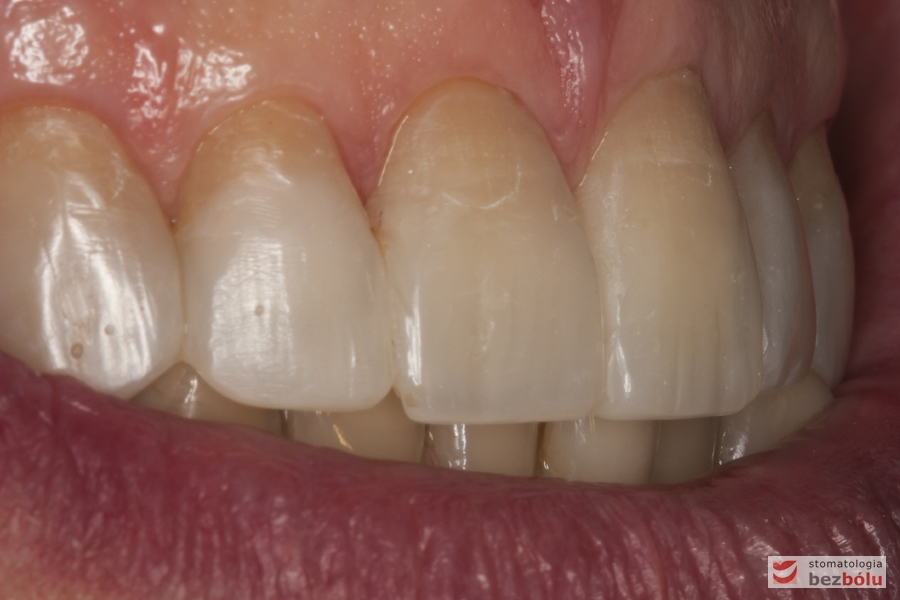

Zęby przednie w szczęce - bezpreparacyjna addycyjna rekonstrukcja materiałem kompozytowym

Zęby przednie w szczęce – bezpreparacyjna addycyjna rekonstrukcja materiałem kompozytowym